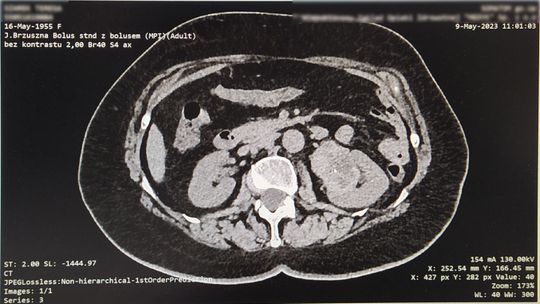

Drugi przypadek dotyczy pacjentki, która miała guza umiejscowionego w bardzo trudno operowalnym miejscu. Guz był wciśnięty pomiędzy żyłę i tętnicę nerkową, dwie najważniejsze arterie odżywcze dla nerki, przy samej jej strukturze. Istniała konieczność preparowania milimetr po milimetrze, na małej przestrzeni, z zachowaniem bardzo dużej ostrożności, z uwagi na bliskość głównych naczyń krwionośnych. Guz w całości usunięto pozostawiając nerkę w nienaruszonym stanie. Zabieg wykonano w technice klasycznej otwartej, z uwagi na wielkość guza. Pacjentka czuje się dobrze.